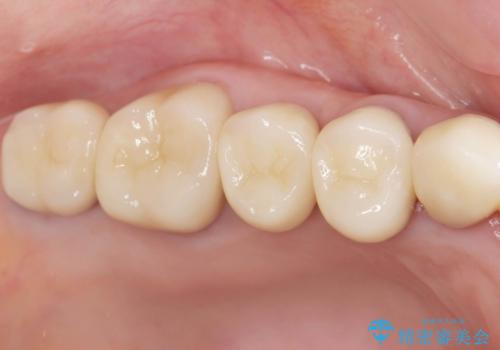

自然な仕上がりとインプラントによる咬合機能の回復に満足いただくことができました。

装着されているクラウンを除去し、自然な色調のジルコニアクラウンによる審美生の改善、インプラントを用いた欠損部の機能回復を計画します。